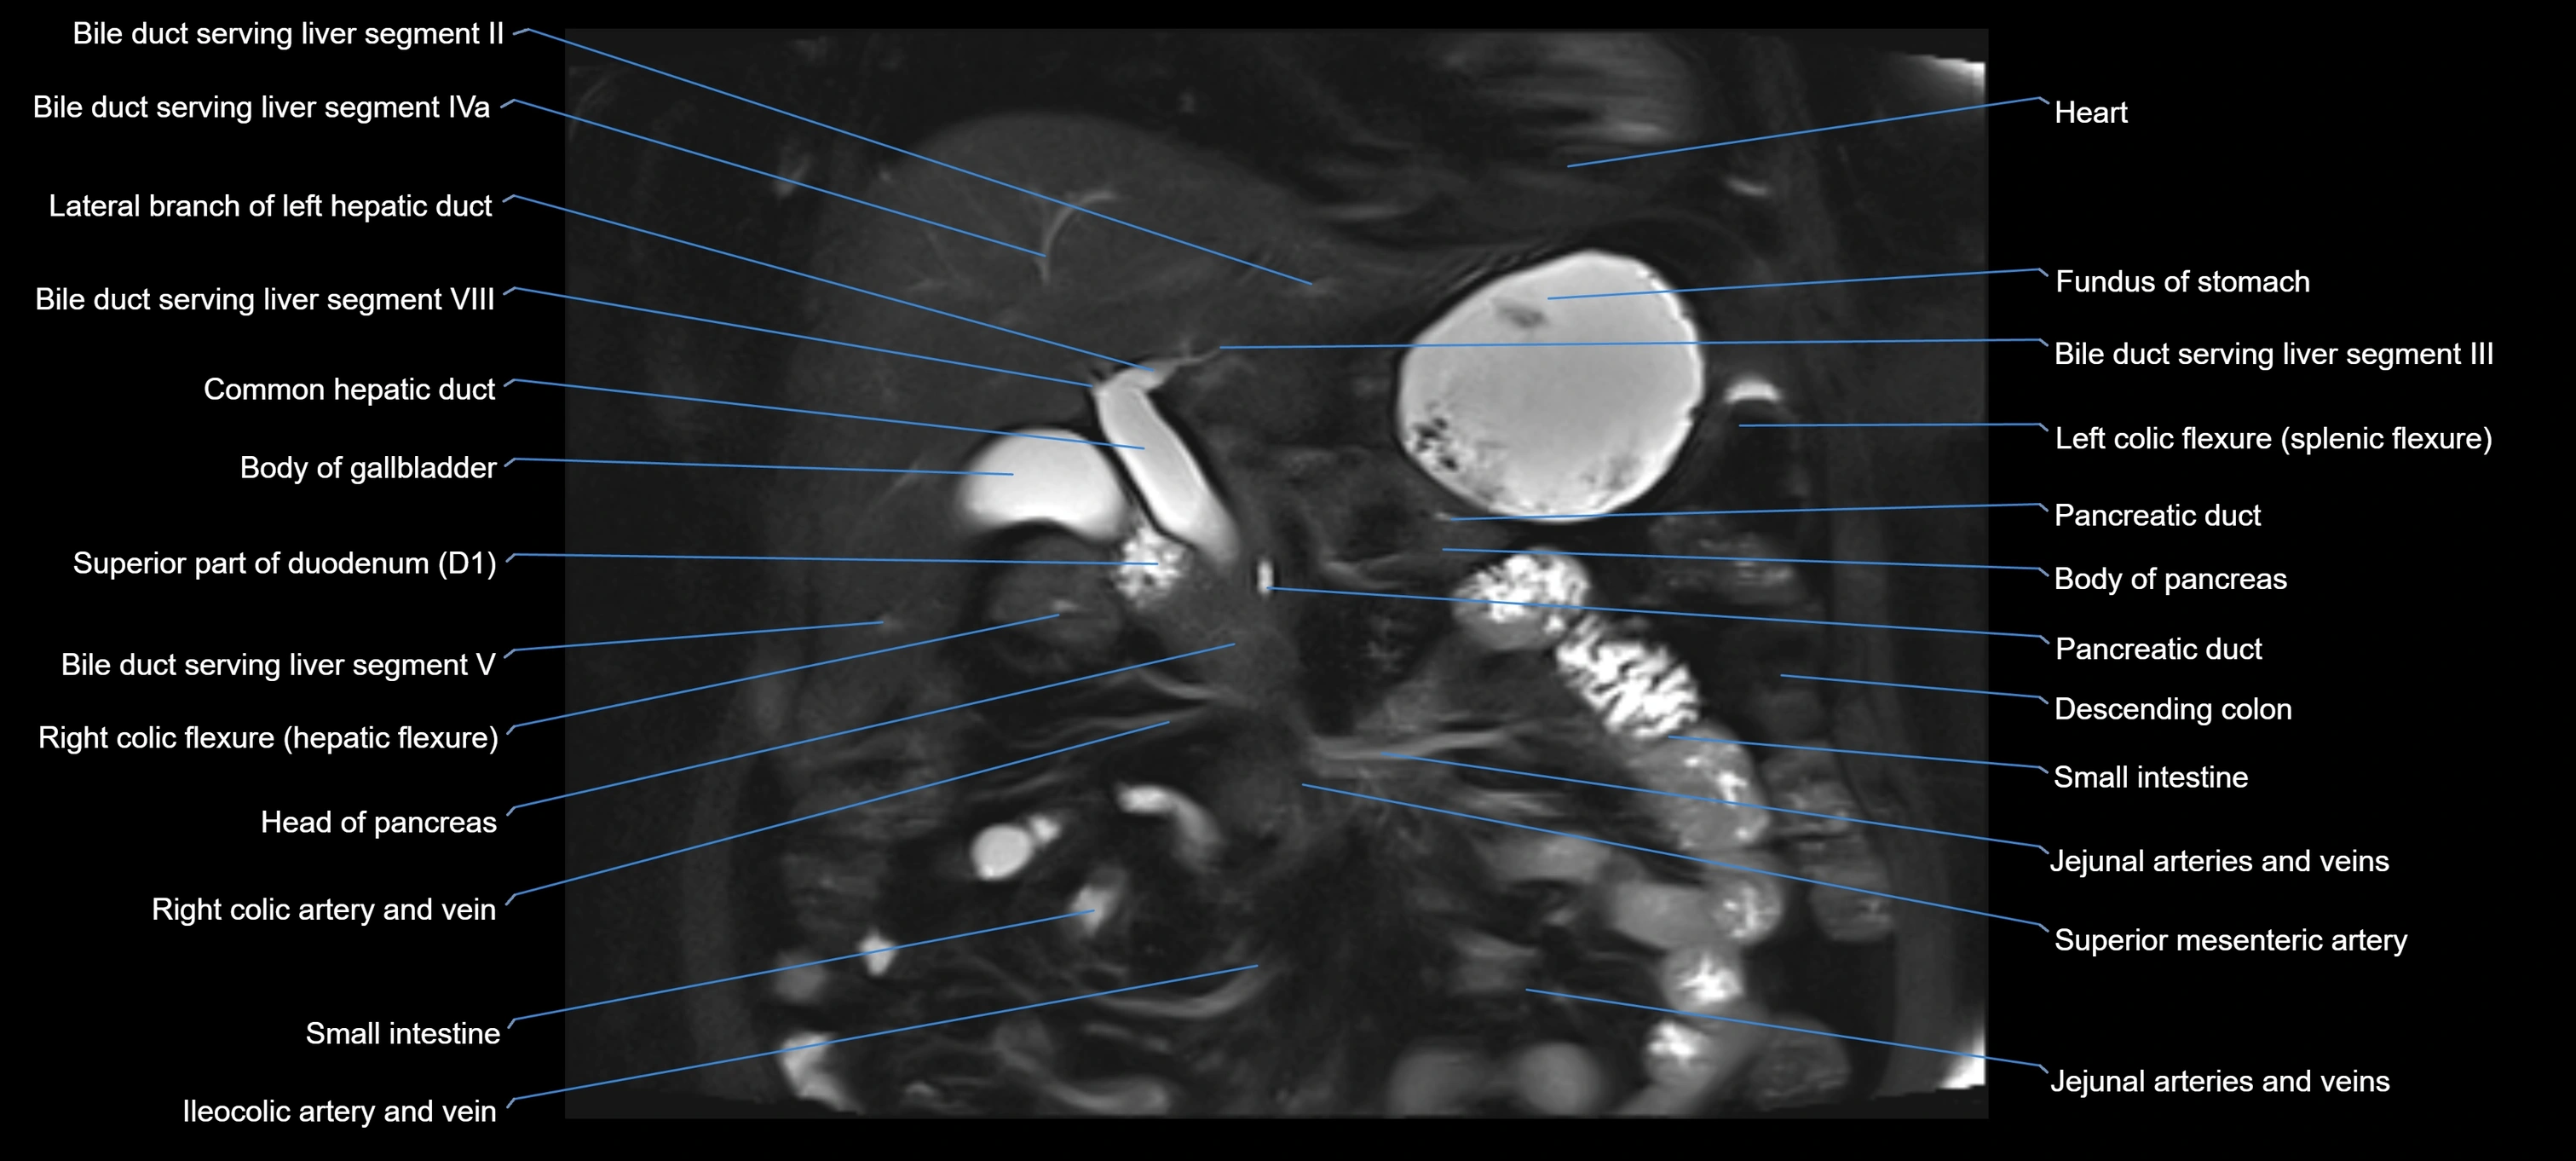

MRI image

image